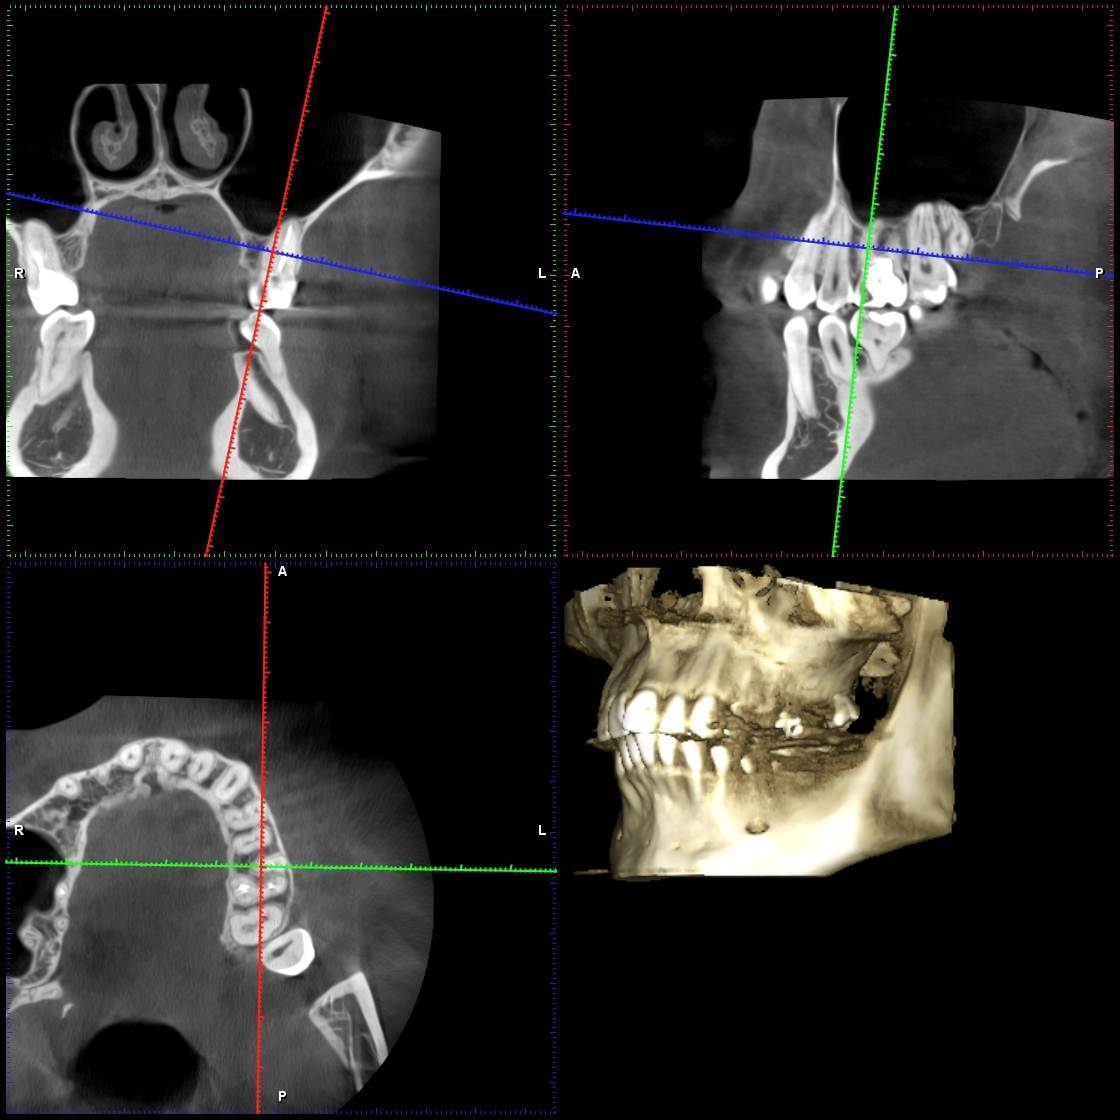

Дарья21 Опубликовано 9 февраля, 2025 Поделиться Опубликовано 9 февраля, 2025 Здравствуйте! Такая проблема…В сентябре лечила зуб, удалили каналы, запломбировали, поставили штифт. С того дня болит этот зуб не прерываясь каждый день. Каждый день приходится пить обезболивающие. Сделала кучу снимков, в том числе 3д снимок, врачи разводят руками, говорят, что на снимке всё в норме. Пробовала подтачивать пломбу, пила антибиотики, ходила на физиопроцедуры, полоскала разными травами. Боль никуда не уходит и не утихает. Стоматолог еще в октябре сказала: «Нет смысла лезть туда и еще раз пломбировать, так как по снимку всё в норме». Но прошло уже 5 месяцев, невозможно с этой болью жить… Подскажите пожалуйста, что это может быть и что делать, снимок прилагаю. ( Зуб 26) Заранее спасибо! Ссылка на комментарий

сирена Опубликовано 13 февраля, 2025 Поделиться Опубликовано 13 февраля, 2025 Выложите сюда кт (3D снимок), я думаю, что может болеть этот зуб. Полгода пить лекарства это ненормально. Ссылка на комментарий

Дарья21 Опубликовано 25 февраля, 2025 Автор Поделиться Опубликовано 25 февраля, 2025 https://disk.yandex.ru/d/2p8qT4ezFe-8OQ Ссылка на 3д снимок. Спасибо всем, кто отвечает) Ссылка на комментарий

wladdX Опубликовано 25 февраля, 2025 Поделиться Опубликовано 25 февраля, 2025 Коллеги, может есть ещё один к\канал в медиальном щёчном корне? Ссылка на комментарий

Carioznik Опубликовано 26 февраля, 2025 Поделиться Опубликовано 26 февраля, 2025 21 час назад, wladdX сказал: Коллеги, может есть ещё один к\канал в медиальном щёчном корне? Есть, мб2- пропущен 1 Ссылка на комментарий

Carioznik Опубликовано 26 февраля, 2025 Поделиться Опубликовано 26 февраля, 2025 (изменено) В 09.02.2025 в 06:00, Дарья21 сказал: Подскажите пожалуйста, что это может быть Исходя из КТ - у Вас есть один необработанный канал, т.е от туда "недоудален нерв"- скорее всего, в этом и причина. Вам лечили зуб используя оптику (увеличительные очки или микроскоп)? Изменено 26 февраля, 2025 пользователем Carioznik 1 Ссылка на комментарий